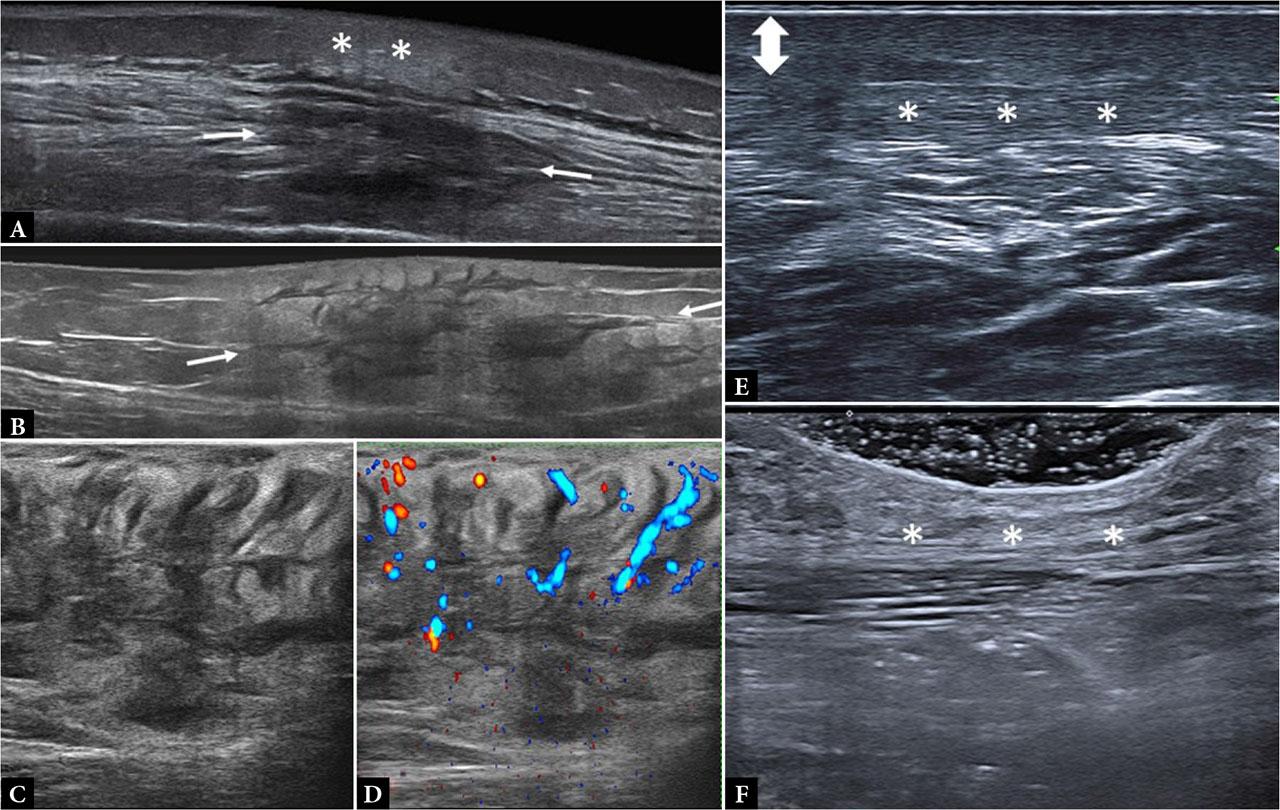

Morphea. Inflammatory phase: A. Extended field-of-view image of the lateral aspect of the leg, showing a lobular panniculitis sonographic pattern in the subcutaneous tissue (**) with muscular regional involvement (white arrows); B. Extended field-of-view image showing a mixed panniculitis sonographic pattern involving the entire thickness of the SAT at the lateral aspect of the thigh; C, D. Same case: B-mode and Power Doppler axial sonograms demonstrating a septal panniculitis pattern with septal hyperemia. Sclerotic phase: E. Increased thickness of the hypoechoic dermis (doble arrow) with thinning of the hypodermis and a fibrillar pattern (*); F. Atrophic phase: normal dermis and severe hypodermis thinning; note the absence of fatty lobules (*)